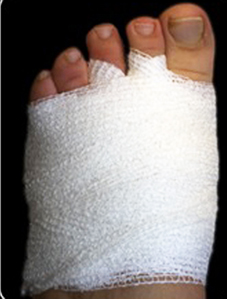

Una vez realizada la osteotomía, las incisiones se suturaron con monofilamento 0000. Se utilizó un vendaje para realizar tracción en los dedos de los pies en dirección medial con una cincha metatarsiana. El paciente salía de quirófano andando con un zapato quirúrgico de suela rígida y plana. Las suturas se retiraron a los siete días y se le mostró cómo cambiar el vendaje para el lavado diario. Se insistió que no debían caminar descalza, sin calzado ni vendaje, para evitar el desplazamiento de las osteotomías (Figura 2).

Figura 2a

Figura 2b

Figura 2. Técnica quirúrgica a) osteotomía DMMO percutánea, b) imagen fluoroscópica de las osteotomías, c) sutura, d) vendaje postquirúrgico con cinchas invertidas para mantener la alineación de los metatarsianos, d, e) vendaje definitivo postquirúrgico, f) paciente al salir de quirófano con apoyo completo y zapato de suela plana y recta